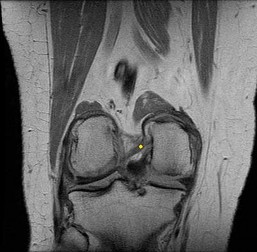

CLINICAL SITUATION FOR QUESTIONS 22 THROUGH 25

A 22-year-old man sustains an injury to his right knee in a motor vehicle collision. Figure 22a is the posterior stress radiograph of the involved knee, and Figure 22b is a selected MR image that identifies the injured structure.

Which relationship is noted for the structure identified by the arrow in Figure 22b? 24

- The anterolateral bundle is tensioned in mid flexion, and the posteromedial bundle is tensioned in both extension and high flexion.

The stress radiographs demonstrate posterior instability of the right knee in flexion. The MR images demonstrate injury to both the anterior and posterior cruciate ligament (PCL), with the stump identified with the arrow on the MR image (Figure 22b). The PCL has 2 functional bands. The anterolateral bundle originates from the roof of the intercondylar notch. It runs in a posterolateral direction onto the tibial crest between the posterior attachment of the medial and lateral menisci. During a double-bundled posterior ligament reconstruction, the

anterolateral bundle is tensioned with the knee in a position of mid flexion. The posteromedial bundle has a variable pattern of tension both in extension and in high flexion. Tensioning of the posteromedial bundle in extension may contribute to resistance against knee hyperextension.